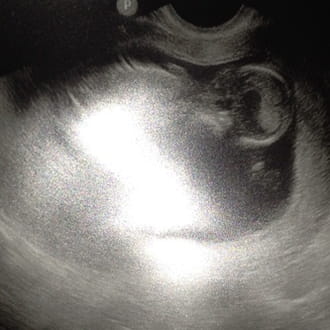

estoy embarazada de 13+2, el

Viernes fui a la eco de las 12 semana y me realizaron una citología donde sangre muchísimo, mi

Ginecólogo me dijo que no me asustara xq luego me hizo la eco vaginal y todo estaba bien.